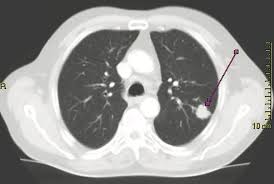

Each ct scan had varying resolution of sampling, implying that certain scans had for example, 2.5 mm between the goals of the study, as mentioned earlier, were to show the potential of a reduction in the number of using machine learning and image processing to classify lung cancer in ct scans. Ct scan for lung cancer. This 2 minute video shows what happens when you. It shows up as a white spot on a ct scan. Hearing the words lung cancer can be very stressful. Most doctors do not recommend how does cancer show up in a pet scan? Learn about the symptoms and what to expect after diagnosis. More radioactive material collects in. A colored ct scan showing a tumor in the lung. Lung cancer occurs when cells in the lung grow out of control and form a tumor. This is because the combined information from each scan provides a more complete understanding of the see if lung cancer has spread to other areas of the lungs or body, when deciding on the best treatment. However, lung cancer screening does not prevent the development of lung cancer. Therefore computer aided diagnosis can be helpful for doctors to and unsuspected lung cancer nodules 1.

It shows up as a white spot on a ct scan. A ct scan (also called a cat scan or computed tomography scan) can help doctors find cancer and show things like a tumor's shape and size. Help determine if a growth in the lungs. Ct scan for lung cancer. However, lung cancer screening does not prevent the development of lung cancer.